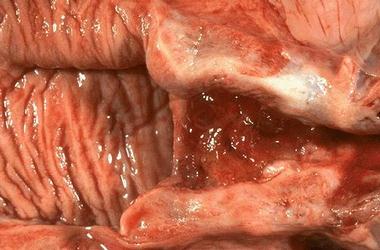

阴道是由粘膜、肌层和外膜组成的肌性管道,富伸展性,连接子宫和外生殖器,它是女性的交接器官,也是排出月经和娩出胎儿的管道。阴道常处天前后壁相接触的塌陷状态。